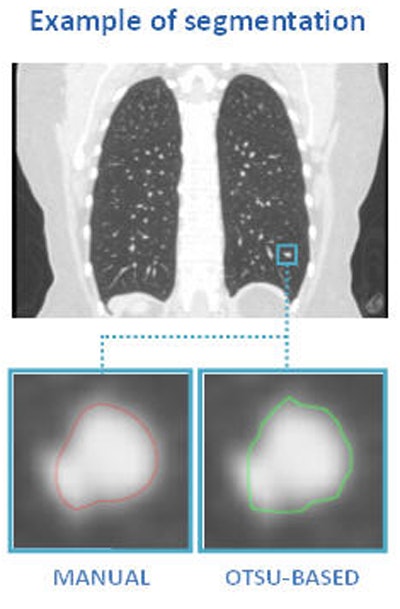

Above, nodule contouring by manual and semiautomated techniques. Below, agreement between nodule contouring measurements is only moderate between the two techniques, but classification results are uniformly high for both techniques. All images courtesy of Julien Willaime, PhD.For evaluation, they contoured each nodule manually using a commercial software program (XD3, Mirada Medical), and also using a proprietary semiautomatic Otsu thresholding method. In all, the investigators extracted 792 texture features from each contour. The most discriminative 20 features were then chosen for each segmentation technique, and a support vector regressor function was used to map the features onto malignancy probabilities (method validated by Lee et al, RSNA 2014).

Overall, they found that volumes derived from manual (mean 945 mm3) were slightly greater and more varied than the volumes derived from the Otsu method (mean 632.66 mm3).

"In terms of agreement, we had moderate agreement between the two segmentation techniques," with a median DICE score of 0.82, Willaime said.

The mean DICE score was 0.76 ± 0.21 (mean ± SD), and agreement between feature values was high (95% CI was less than 0.23 in all cases).